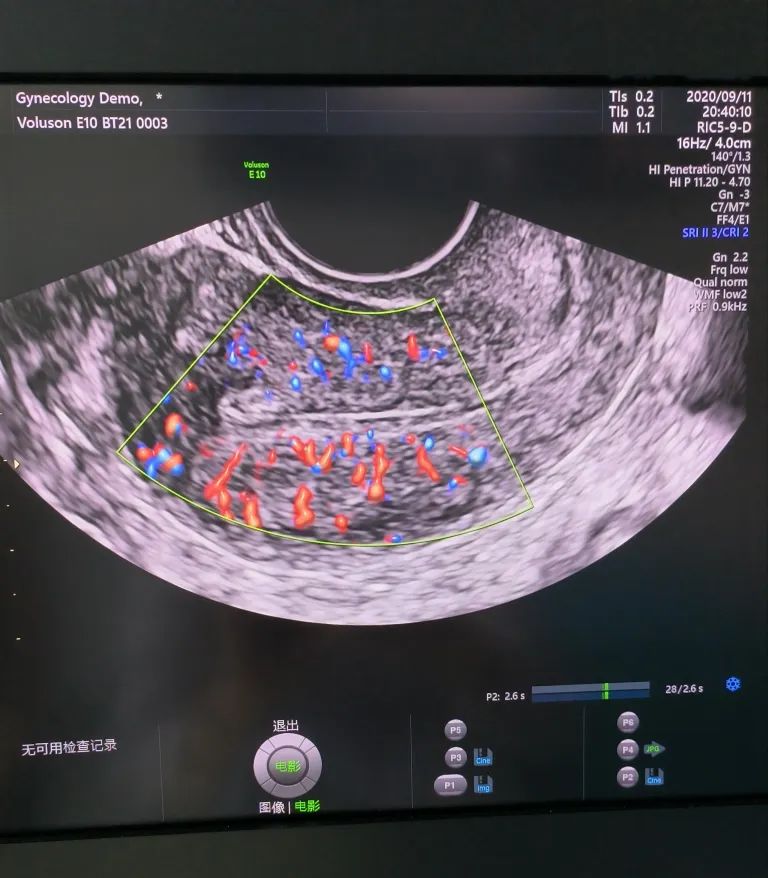

經陰道超聲是在陰道超聲探頭上套上避孕套,將探頭伸入陰道進行檢查。由于探頭位置接近子宮和卵巢,圖像更清晰,檢查結果更準確。而且不需要憋尿,相對節(jié)省時間。所以現(xiàn)在大部分醫(yī)院對有性生活史的婦女更愿意開展經陰道超聲檢查。